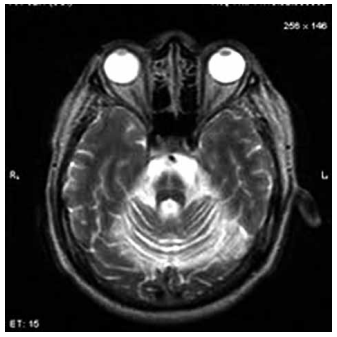

Homem de 68 anos apresenta lentificação progressiva dos movimentos, rigidez muscular e instabilidade postural há três anos. Inicialmente, o quadro foi interpretado como Parkinsonismo, mas a evolução clínica revelou pobre resposta à levodopa, quedas frequentes, disautonomia e sinais cerebelares. A ressonância magnética do encéfalo, a seguir, demonstrou atrofia do putâmen e do cerebelo, com hipersinal na ponte (hot cross bun sign).

Diante desse quadro clínico, qual é o diagnóstico mais provável?